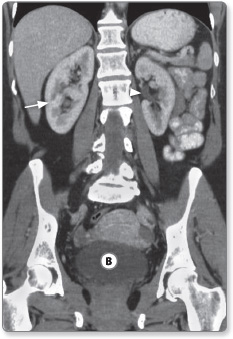

The kidneys are located at the posterior wall of the abdomen in the retroperitoneal region. They extend from approximately the 11th rib to the iliac crests. The right kidney is located slightly lower than the left due to the large size of the liver. The external or lateral border is convex, whereas the internal border is concave, and contains a deep notch, which is known at the hilum of the kidney (Figure 1.9). The renal vessels, nerves and uterus enter the kidney at the hilum.

The adult kidney varies in length between 8 and 12 cm. The arterial supply is via the renal arteries that arise from the aorta. Each renal artery divides into four or five branches on entering the hilum. The ureters run downwards from the hilum to the bladder and in their course rest on the psoas muscles. At the pelvic brim they cross the common iliac artery before entering the bladder.

Figure 1.9: Coronal CT image showing the kidneys (arrow) and bladder Ⓑ. The hilum of the left kidneys is visible (arrowhead).